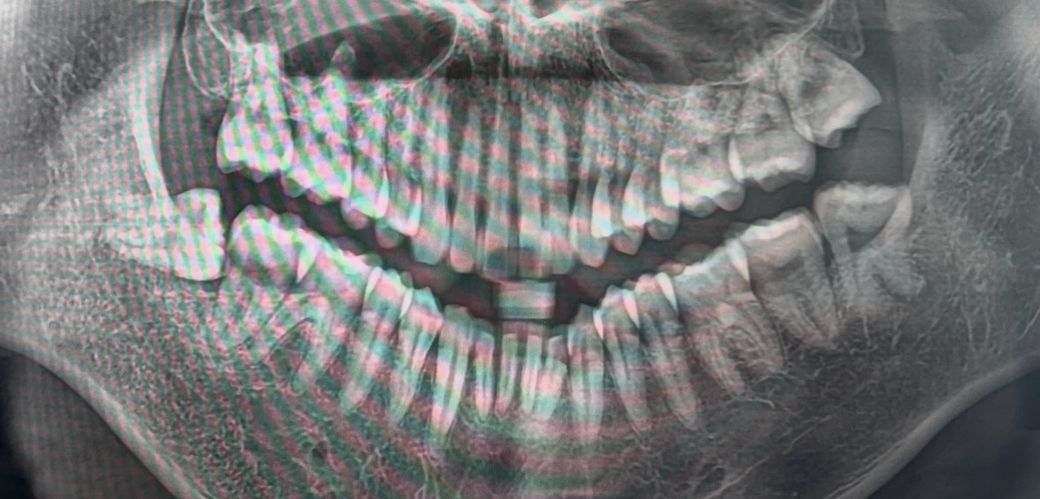

차례대로 사랑니발치전, 발치후, 가까이서 찍은 엑스레이입니다…

• 1번 째 사진